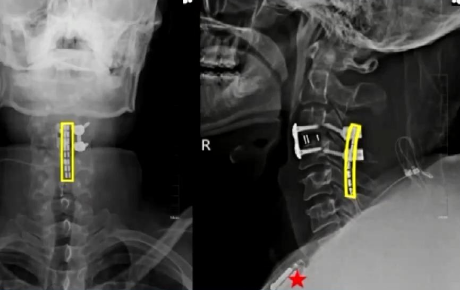

面对这一严峻挑战,医生吴敏飞团队作出了大胆尝试:将脊髓接口技术直接应用于患者颈髓段。吴敏飞介绍,颈脊髓损伤意味着大脑与脊髓之间的联系完全中断。而脊髓接口技术通过在损伤部位精准植入微型电极装置,激活并控制肢体运动神经元,使患者能够重新支配瘫痪的肢体活动。

手术取得圆满成功。经过两周持续优化的精准神经调控,刘博奇的四肢肌力显著恢复。三个月后,团队为他量身定制了脊髓接口+外骨骼机器人协同康复方案。在脊髓接口的精准调控与外骨骼机器人的辅助支撑下,刘博奇成功迈出了受伤后的第一步。